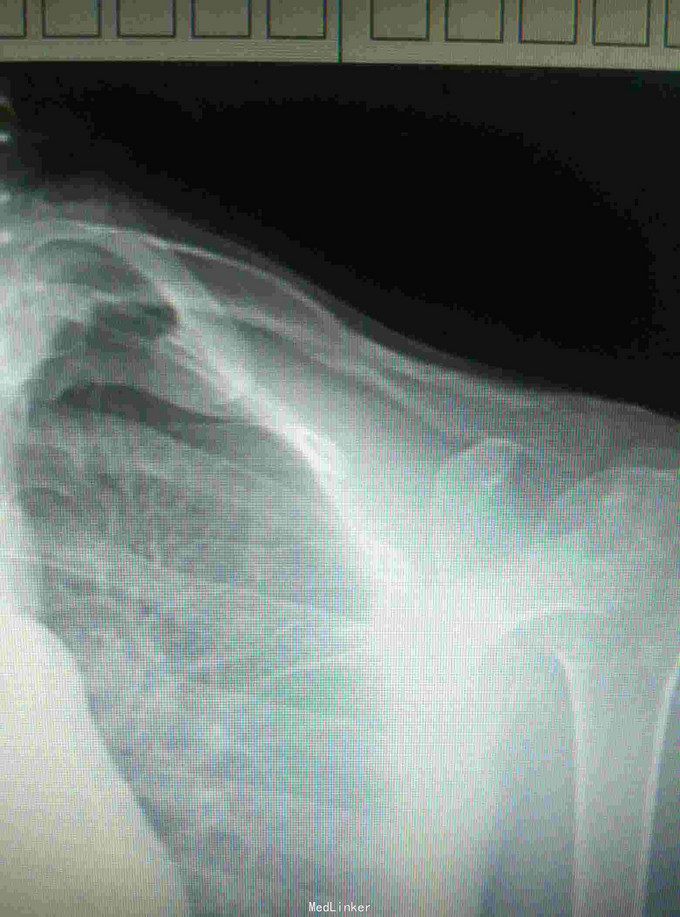

诊断:左锁骨骨折, 治疗:闭合复位TEN固定术

术后恢复良好,术后4个月拔除TEN 讨论:大部分锁骨骨折可以通过闭合复位钢针固定,但如果是骨质疏松病人,容易出现松动或退针等可能。而TEN更具有抗弯曲稳定,抗旋转稳定,横向稳定,轴向稳定,所以骨质比较疏松患者,我们采用TEN进行固定。